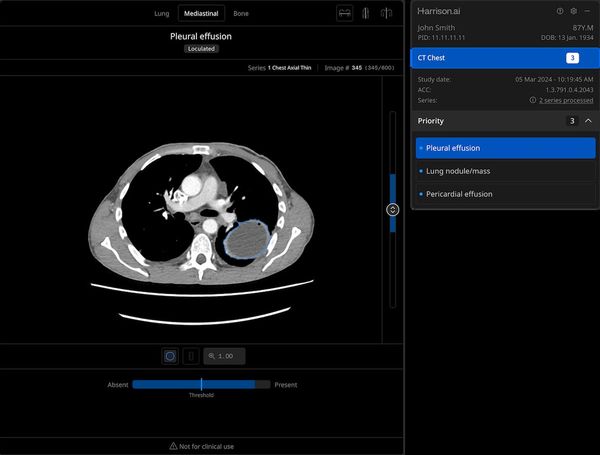

FDA Clears CT-Based AI Triage Platform from AidocLatest News

FDA Clears CT-Based AI Triage Platform from Aidoc